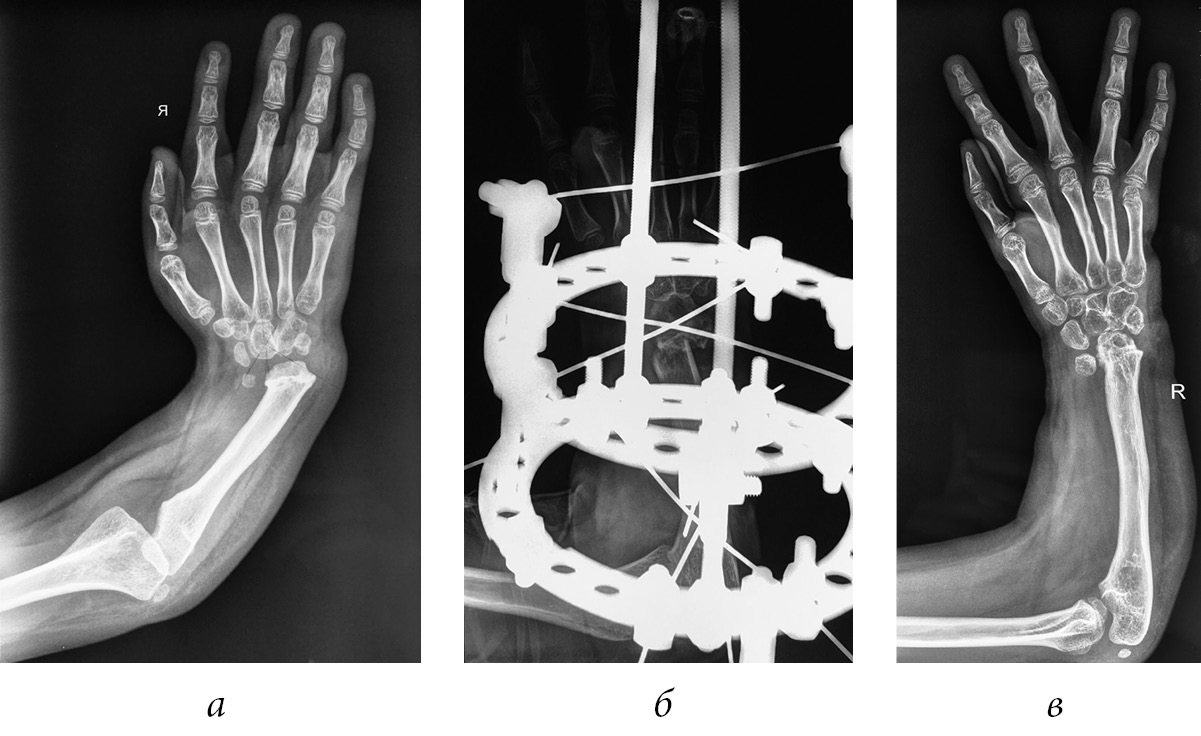

A clinical example of surgical treatment of the group 1 patient (Fig. 1)

Fig. 1. Radiograph of the upper limb of patient P., 5 years old, before elongation of the ulnar bone (a), after osteotomy (b), at the end of the fixation period (c) and after 3 years (d, e)

Patient P., 5 years old, was admitted to the department with a diagnosis of congenital right-sided radial clubhand, along with aplasia of finger I. Previous surgery included the right-hand centering.

Clinical examination revealed shortening of the right forearm by 4 cm, aplasia of the radial bone, and radial deviation of the right hand of 15°. Moreover, the hand was impossible to bring to the middle position passively, and aplasia of the finger I of the right hand was reported (Fig. 1, a). Given the slight deviation of the hand and the apex of the ulnar deformity in its proximal part, we decided to perform osteotomy in the upper third of arm. The postoperative period was uneventful. The ulnar bone was extended by 3.7 cm, and the correction of the ulnar bone deformity was 25°. Subsequently, pollicization of the ray II of the hand was performed on the affected side.

After 3 years, the radial deviation of the hand was found to be 20° during the clinical examination, which was the state of hand after pollicization of finger II of the right hand. Ranges of movements in the elbow joint and fingers were found to be adequate. The child served himself and did not complain actively. Parents were satisfied with the result.